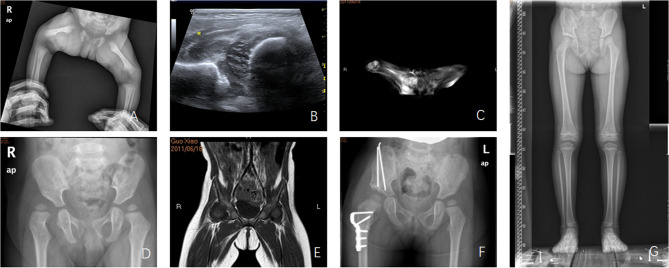

Outcome of infantile septic arthritis of the hip joint: A two-children medical center's experience.

期刊介绍: BMC Musculoskeletal Disorders is an open access, peer-reviewed journal that considers articles on all aspects of the prevention, diagnosis and management of musculoskeletal disorders, as well as related molecular genetics, pathophysiology, and epidemiology. The scope of the Journal covers research into rheumatic diseases where the primary focus relates specifically to a component(s) of the musculoskeletal system.